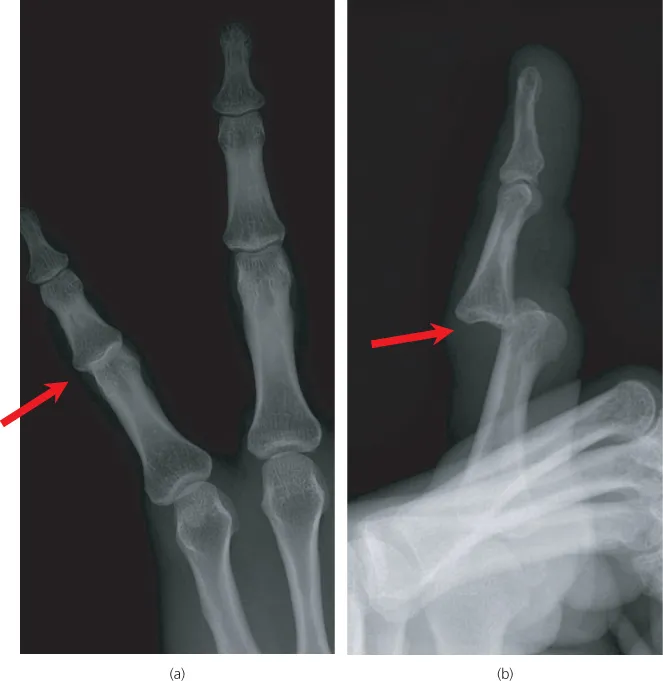

- Two views—one view is always one view too few

Rule 1—two views (‘One view is always one view too few’)